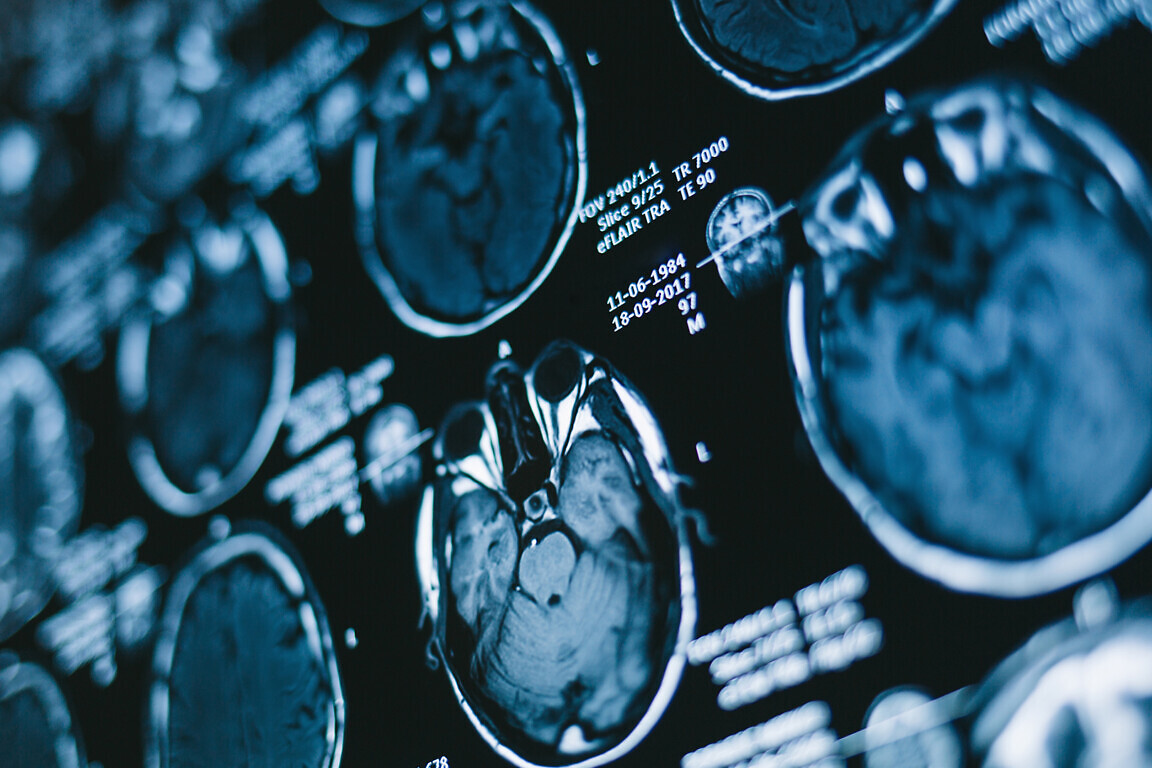

The news follows the announcement in mid-September that Colwyn Bay, Ysbyty Glan Clwyd, Wrexham Maelor and Ysbyty Gwynedd hospitals would all receive X-ray equipment with better image quality and reliability as part of a £4.4 million investment from the government.

The investment will see older X-ray machines replaced with new, updated digital radiology systems. This will ensure image quality is improved and radiation exposure is reduced, as well as being easier for staff as they are much more comfortable to use and are fully automated for positioning.

New fluoroscopy systems, which are useful for reviewing the swallowing action and radiological procedures such as biopsies or drainages, will be provided at Wrexham Maelor Hospital and Ysbyty Gwynedd.

Mammography imaging equipment, which is used to examine the breast and is vital in helping to detect cancer and other breast diseases, will also be replaced at Wrexham Maelor Hospital and Ysbyty Gwynedd.